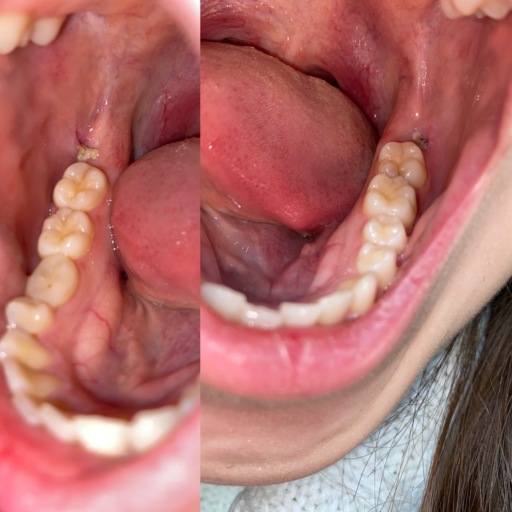

Teeth bent and twisted and a lot of pain given

For a long time I have been expriencing a lot of pain I'm my teeth when I eat drink and not do anything with them, when I eat I go through a lot of pain and feel sick and light headed because of it. My teeth are twisted and bent and one of them which is my adult tooth and another one which is my adult tooth feels like it's going to fall out which gives me more pain as they have been pushed backwards and forwards and I'm looking on some advice to do.